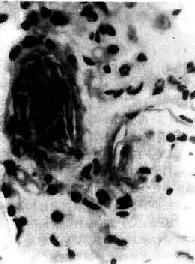

图3-9 肺羊水栓塞 小血管内有角化上皮 (五)其他栓塞 肿瘤细胞栓塞,可引起肿瘤在局部形成转移瘤(图3-10)。寄生虫、虫卵和其他异物偶可进入血循环引起栓塞。

图3-10 肺小动脉腔内肝癌细胞栓子